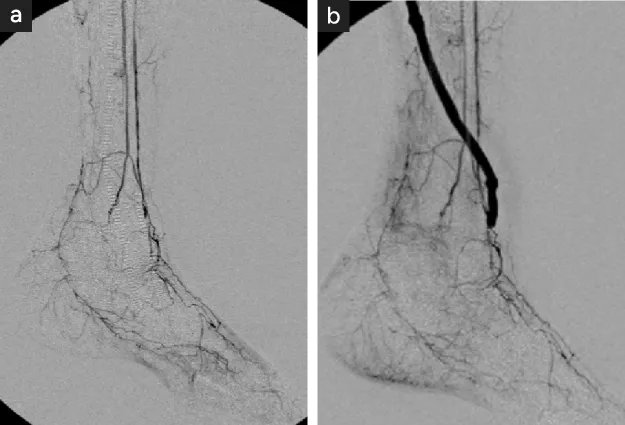

図12

図12. 腎移植例のASO

54才/女性/糖尿病/CLTI/WIFI 222/腎移植後17年

• バイパス前足部動脈病変が高度に進行

• バイパス可能な部位が限定される